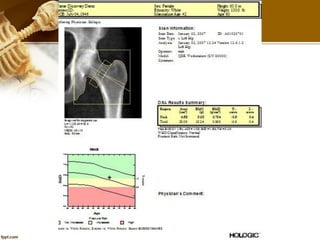

 Correct Hip ROI

• The Femur image shows the

greater trochanter (1),

femoral neck (2), and ischium

(3).

• A minimum of three

centimeters of tissue should

be shown above the greater

trochanter and below the

ischium.

AP Hip Exam

 Hip ROI

• Use femoral neck, or total

proximal femur whichever is

lowest.

• BMD may be measured at

either hip.

• Internal rotation of femur so

that no or little lesser

trochanter is visualized.

The Neck ROI should positioned as

follows:

• The Neck ROI includes no part

of the greater trochanter

• The Neck ROI includes soft

tissue on either side of the neck

• The Neck ROI is perpendicular

to the femoral neck

• The Neck ROI contains little or

no ischium